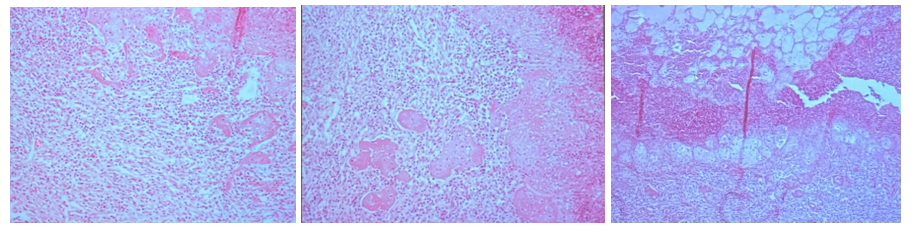

196. Leucosis lymphadenoidea hepatitis (Lymphosarcoma)

Description: At one end there is basophilic stained tumor tissue formed by slightly differentiated lymphocytes. Tumor tissue arises from portal and bile tracts (sign of liver lymphoid leukemia) gradually invades the center of the lobules, and may substitute them. In some parts of normal tissue, hemorrhagic tracts arise after migration of parasitic larvae.

Etiology: Viral infection, such as Marek’s disease in young birds.

Pathogenesis: Leukosis is a tumor of lymphocytes, but when the tumor is malignant the proper term is lymphosarcoma. Leucosis originates either in lymph nodes or in bone marrow, and metastasis is a characteristic feature. Tumor gradually replaces normal liver tissue which can lead to the death of the animal.